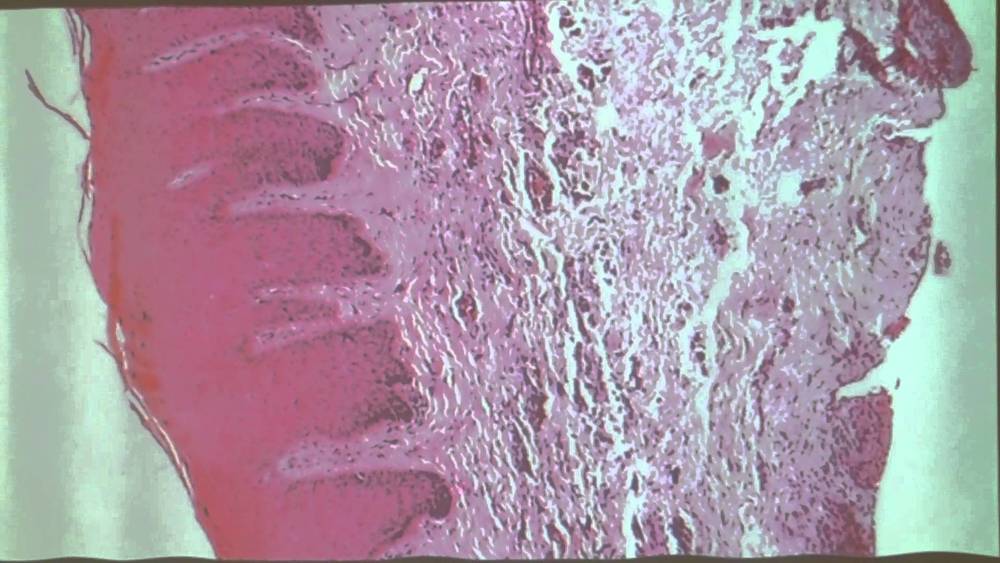

2. Estructura Histológica: La encía está compuesta por un resvestimiento epitelial de tipo masticatorio y un tejido conectivo. subyacente llamado lámina propia o corion.

1. Estructura Histológica de la encía libre: una vertiente externa o bucal, y otra vertiente interna o dental, que se denomina epitelio del surco y que delimita una hendidura entre la lengueta y el diente.

1. El epitelio de la encía libre está conectado por una interfase sumamente ondulada, debido a las proyecciones papilares que envía el tejido conectivo hacia el epitelio y la presencia de crestas epiteliales interpapilares. Estas crestas son menos prominentes en las personas de mayor edad y más marcadas en jóvenes.

2. Estructura histológica de la encía adherida:

1. Epitelio: es de tipo estratificado plano queratinizado ofreciendo el estrato córneo distintos grados de queratinización. Presenta menos cantidad de glucógeno que el epitelio no queratinizado, por la relación que existe entre esta inclusión citoplasmática y el grado de queratinización. También suele observarse mayor cantidad de células de Langerhans y melanocitos.

1. Corion: es de tipo denso, sumamente fibroso. se caracteriza por poseer abundantes papilas delomorfas que levantan el epitelio que lo reviste; la superficie presenta un aspecto puntiforme. Las partes protruyentes corresponden al epitelio más adelgazado.